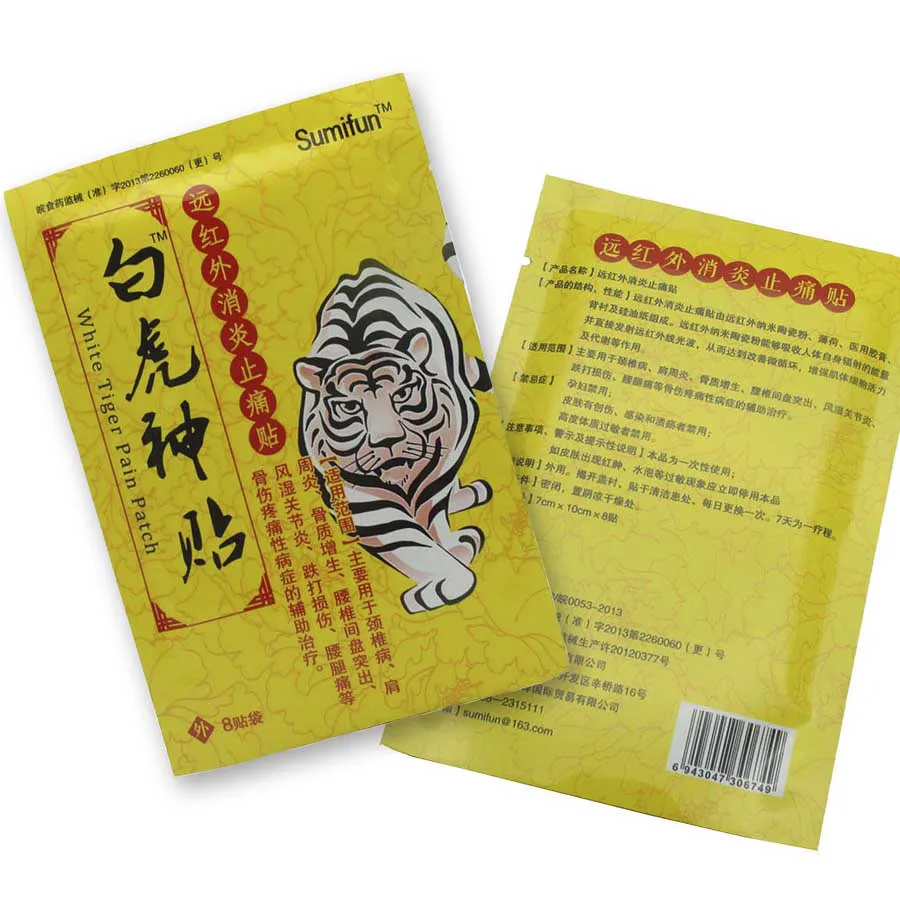

Пластырь от боли CN Herb White Tiger, противовоспалительная анальгетическая паста с дальним инфракрасным излучением, 8 паст